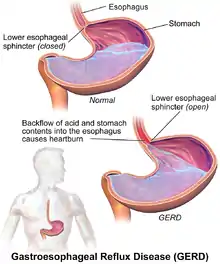

Gastroesophageal reflux disease (GERD) or gastro-oesophageal reflux disease (GORD) is a chronic upper gastrointestinal disease in which stomach content persistently and regularly flows up into the esophagus, resulting in symptoms and/or complications.[6][7][10] Symptoms include dental corrosion, dysphagia, heartburn, odynophagia, regurgitation, non-cardiac chest pain, extraesophageal symptoms such as chronic cough, hoarseness, reflux-induced laryngitis, or asthma.[10] In the long term, and when not treated, complications such as esophagitis, esophageal stricture, and Barrett's esophagus may arise.[6]

Causes

A small amount of acid reflux is typical even in healthy people (as with infrequent and minor heartburn), but gastroesophageal reflux becomes gastroesophageal reflux disease when signs and symptoms develop into a recurrent problem. Frequent acid reflux is due to poor closure of the lower esophageal sphincter, which is at the junction between the stomach and the esophagus.[6]